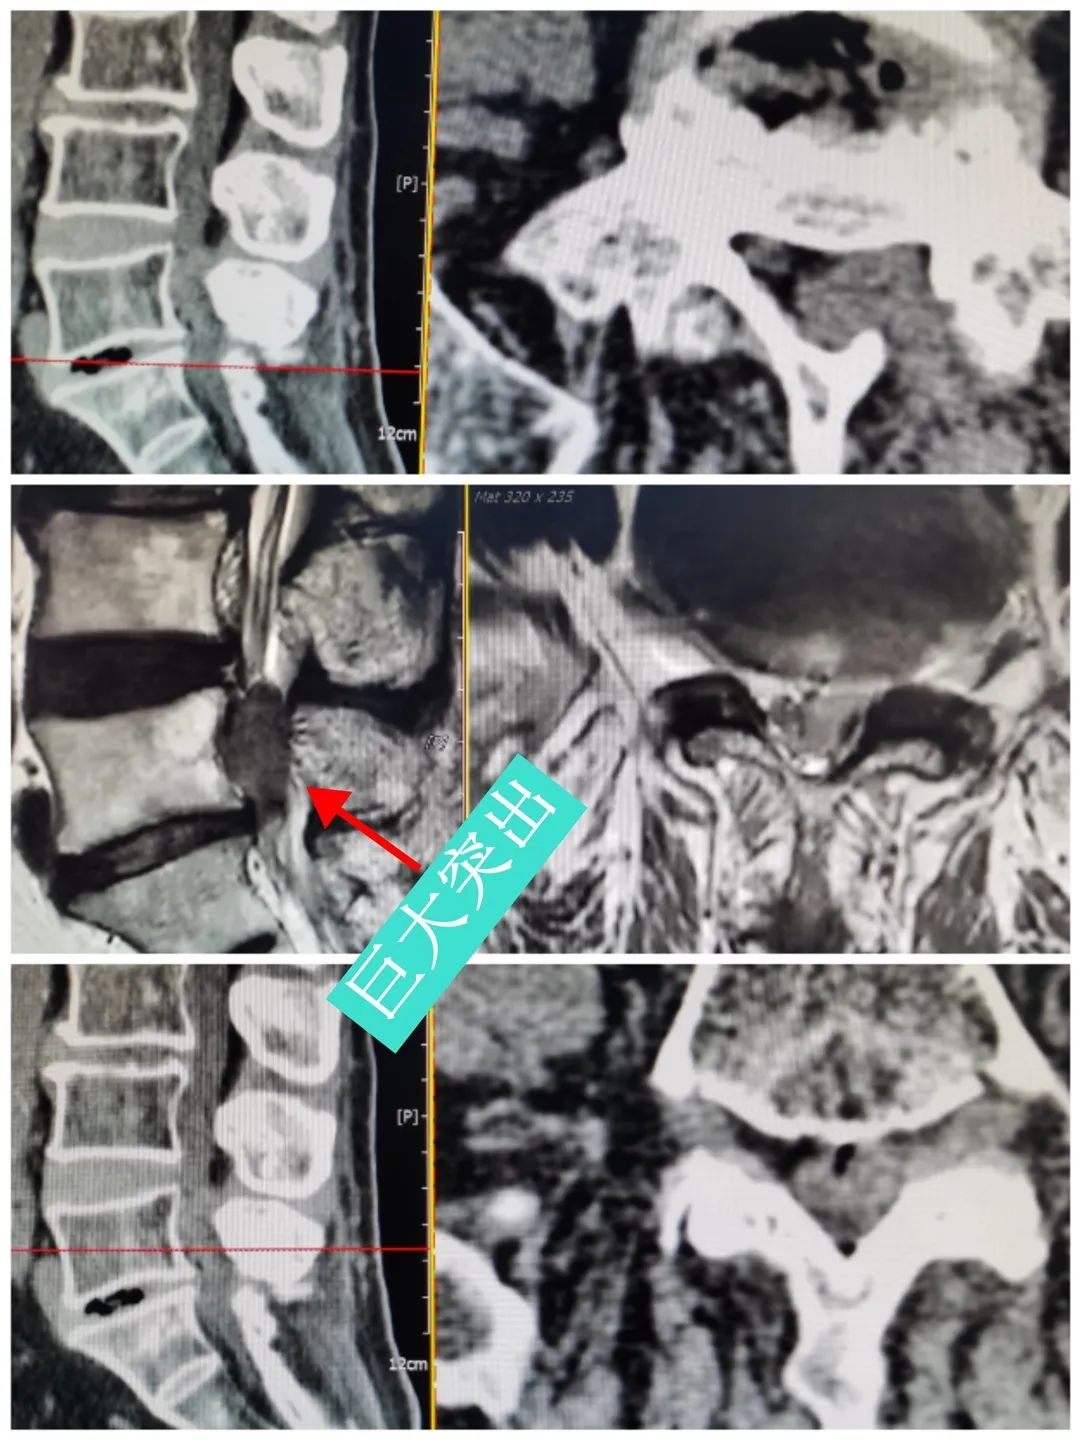

术前影像学检查

脊柱外科微创团队对患者详细查体后,进行病例讨论,详细阅读患者既往及本次住院影像学资料,考虑诊断:腰椎间盘突出症开放单摘减压术后再发并腰椎管狭窄症。结合患者的诉求,最后讨论一致,确定微创单侧双通道脊柱内镜下椎管扩大减压+腰5/骶1椎间盘摘除、射频消融、椎间融合器植骨融合、经皮螺钉内固定术的手术方案。

术日,在精准的皮肤切口定位后,置入双侧通道内镜,内镜下见巨大椎间盘突出、椎管狭窄严重,在陈子华主任指导下,脊柱外科微创团队规范、仔细操作,摘除巨大椎间盘组织后,植入椎间融合器及椎弓根螺钉。术中椎管内减压充分、椎间盘组织去除彻底、脊柱系统得到稳妥固定。术后患者自觉下肢麻痛症状即刻改善,术后第二天,患者在主管医生指导下,佩戴腰围下床活动,状态良好。